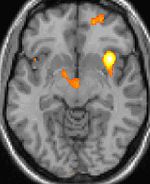

A headache ( cephalalgia in medical terminology) is a condition of pain in the head; sometimes neck or upper back pain may also be interpreted as a headache. It ranks amongst the most common local pain complaints and may be frequent for many people.

The brain in itself is not sensitive to pain, because it lacks nociceptors. Several areas of the head can hurt, including a network of nerves which extend over the scalp and certain nerves in the face, mouth, and throat. The meninges and the blood vessels do have pain perception. Headaches often result from traction to or irritation of the meninges and blood vessels. The membrane surrounding the brain and spinal cord, called the dura mater, is innervated with nociceptors. Stimulation of these dural nociceptors is thought to be involved in producing headaches. Similarly the muscles of the head may be sensitive to pain.